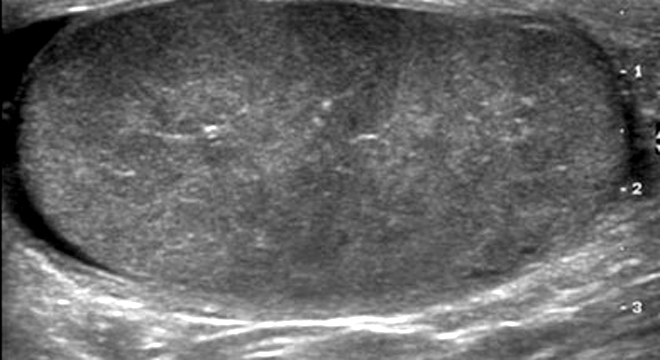

• Ultraschall zum Ausschluss anderer Erkrankungen: z.B. einer Hodentorsion (Verdrehung der Hodengefässe).